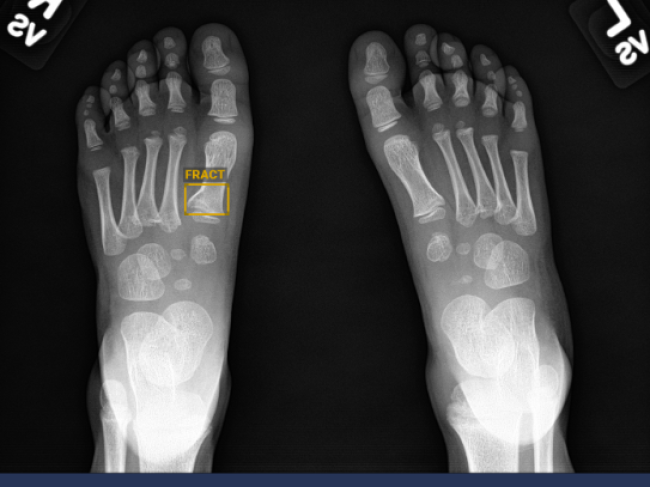

Uma solução inteligente para diagnóstico de lesões de trauma

O BoneView é o primeiro produto da Gleamer desenvolvido para auxiliar radiologistas e médicos na deteção de Fraturas, Derrame intra-articular (cotovelo, joelho, tornozelo), Luxações, Lesões ósseas locais: benignas, malignas ou indeterminadas, em radiografias de Extremidades, Pélvis, Coluna lombar: fraturas por compressão, caixa torácica (grelha costal), através de IA (inteligência artificial).